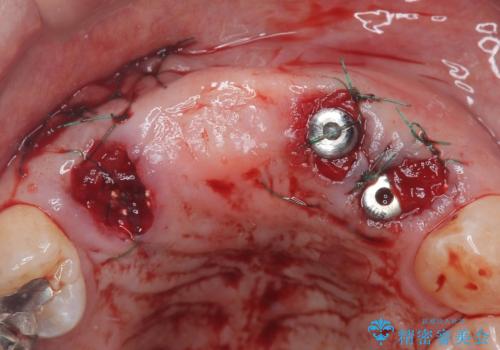

- 歯茎の大きな腫れを主訴に来院された患者様です。前歯5本にはブリッジが装着されていました。レントゲン検査より、右上3番に大きな根尖病巣が認められ、さらに左上1、2番の支台歯にも破折があったため、抜歯を行いました。その後、インプラントを3本埋入し、オールセラミッククラウンのブリッジで補綴しました。

術前のCT画像より、抜歯即時インプラントが可能と判断したため、抜歯と同時にインプラント埋入を行いました。術式にはセミルーナーフラップを用い、唇側の骨吸収を抑える目的でルートメンブレンテクニックを併用しました。